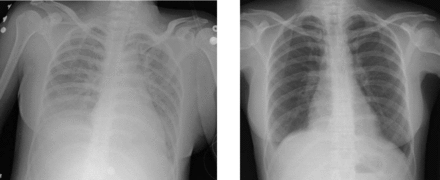

Transfusion-related acute lung injury (TRALI) is a serious blood transfusion complication characterized by the acute onset of non-cardiogenic pulmonary edema presenting with hypoxia following transfusion of blood products.[1]

It is often impossible to distinguish TRALI from acute respiratory distress syndrome (ARDS). The typical presentation of TRALI is the sudden development of dyspnea, severe hypoxemia (O2 saturation <90% in room air), hypotension, and fever that develop within 6 hours after transfusion and usually resolve with supportive care within 48 to 96 hours. Although hypotension is considered one of the important signs in diagnosing TRALI, hypertension can occur in some cases.[3]

TRALI is defined as an acute lung injury that is temporally related to a blood transfusion; specifically, it occurs within the first six hours following a transfusion.[13]

It is a diagnosis upon examination of clinical manifestations that appear within 6 hours of transfusion, such as acute respiratory distress, tachypnea, hypotension, cyanosis, and dyspnea. TRALI is an uncommon syndrome, that is due to the presence of leukocyte antibodies in transfused plasma. It is believed to occur in approximately one in every 5000 transfusions.[3] Leukoagglutination and pooling of granulocytes in the recipient's lungs may occur, with release of the contents of leukocyte granules, and resulting injury to cellular membranes, endothelial surfaces, and potentially to lung parenchyma. In most cases leukoagglutination results in mild dyspnea and pulmonary infiltrates within about 6 hours of transfusion, and spontaneously resolves.